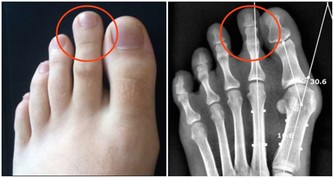

晚上腿腫,變得沒有知覺

這是緩慢靜脈衰竭的表現。需要多吃蔬菜,它們含有能夠加固靜脈壁的纖維。天天可做幾遍腿部保健操。